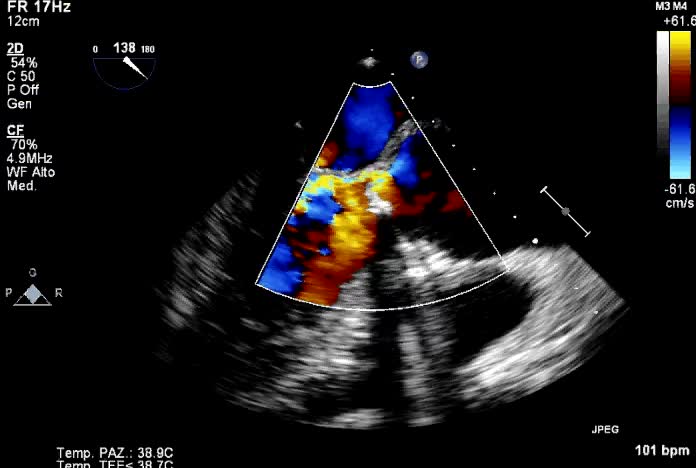

Parole chiave: color diagnosi ecotee endocardite protesi -

Insufficienza protesi aorticaAutore: Andrea Barbieri

Categoria: Videoalbum

Parole chiave: diagnosi ecotee endocardite protesi